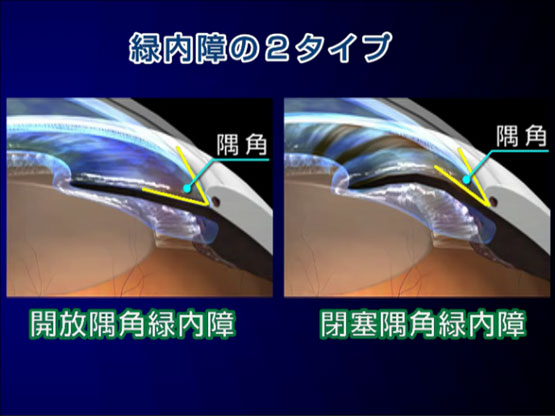

えのき眼科で行われている緑内障治療2 レーザー治療

緑内障の病型により

-

レーザー虹彩切開術

-

レーザー線維柱帯形成術